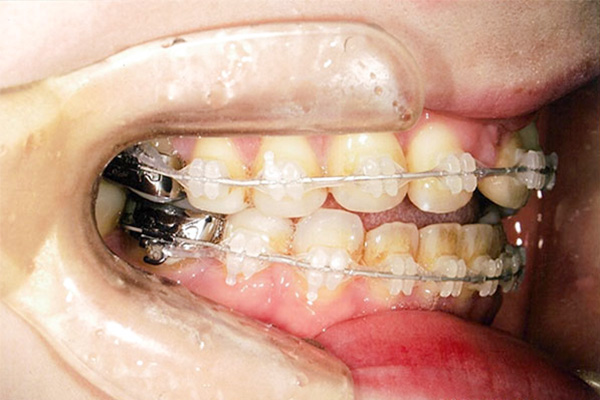

6ヶ月後